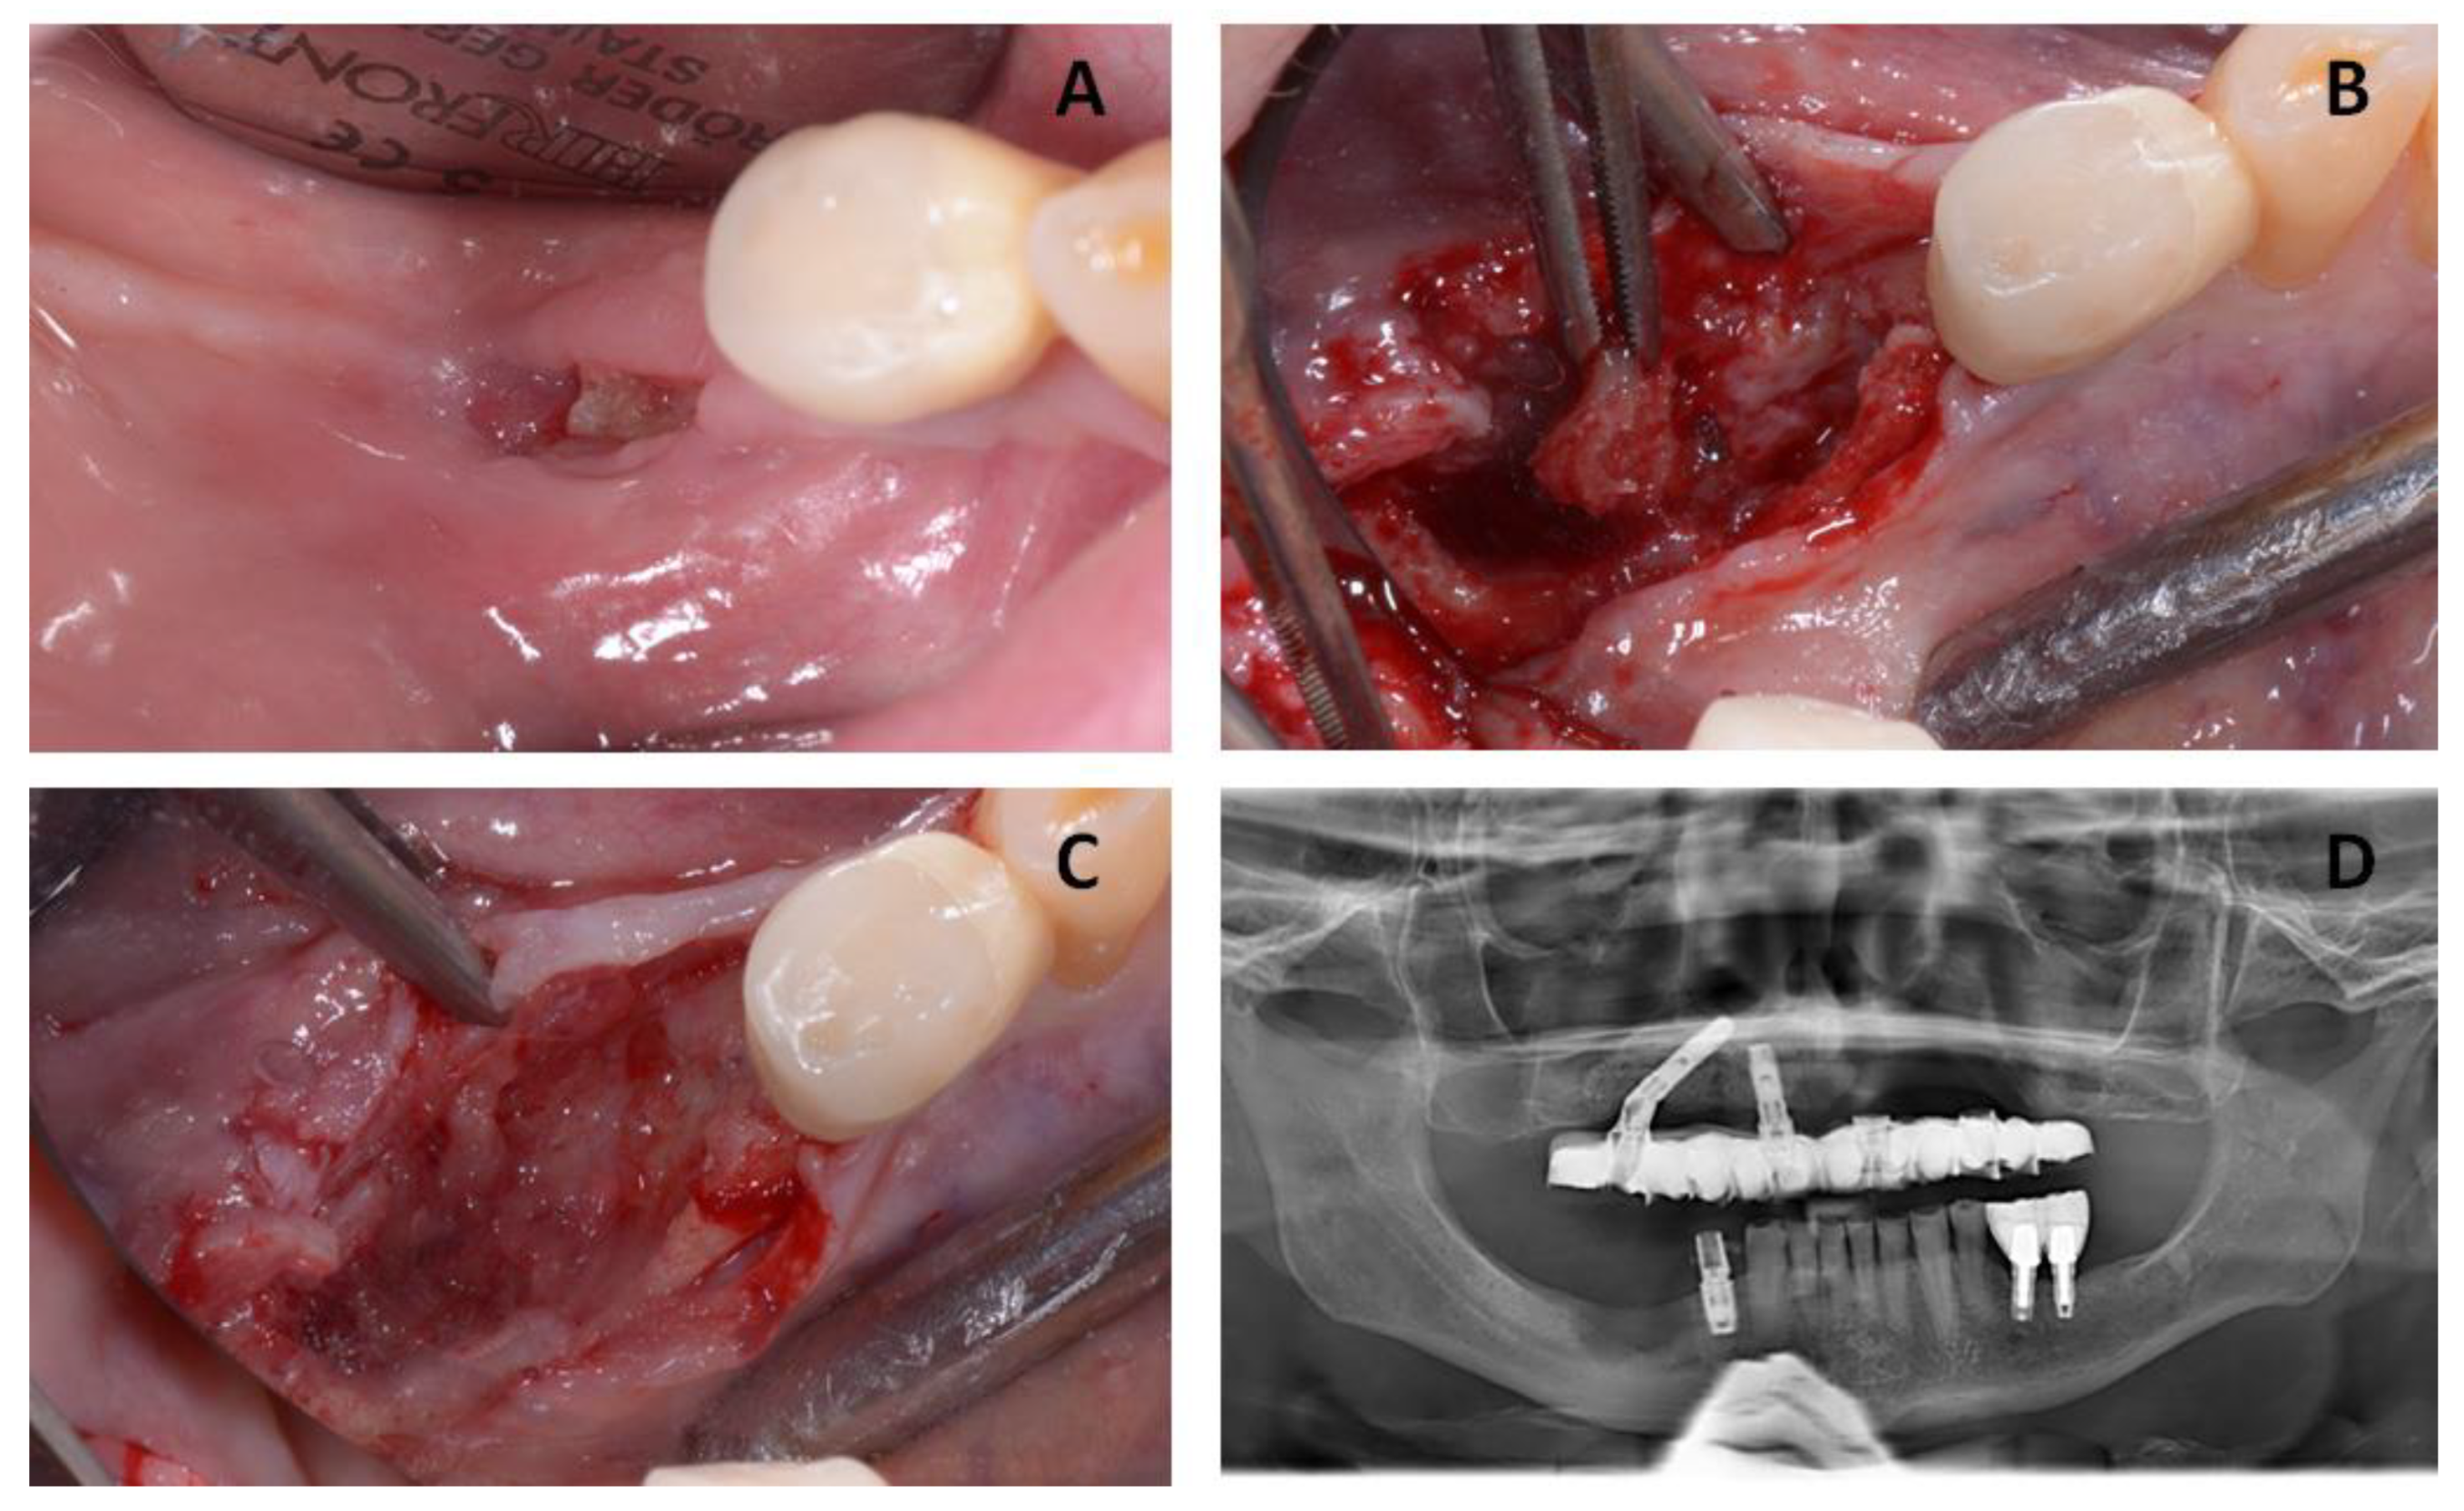

The patient underwent three surgeries in total. The first surgery was scheduled for September 2016 and included removal of the necrotic bone and implant #26 (Figure 2). After a healing period of three months, the All-on-4 prosthesis was placed for function and esthetics.

Figure 1. (A) Radiographic image from the patient showing an MRONJ lesion on the posterior left side of the maxillary bone. (BD) Clinical images from the patient showing an MRONJ lesion on the posterior left side of the maxillary bone.